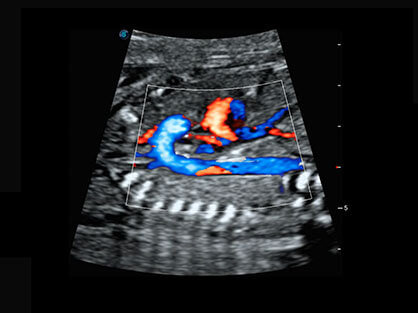

通过对组织运动信息、血流信号及背景噪声进行准确智能的阈值判定,高效提取出微弱血流信号,获得高灵敏度和空间分辨率的血流图像,为临床提供更加真实和丰富的诊断信息。